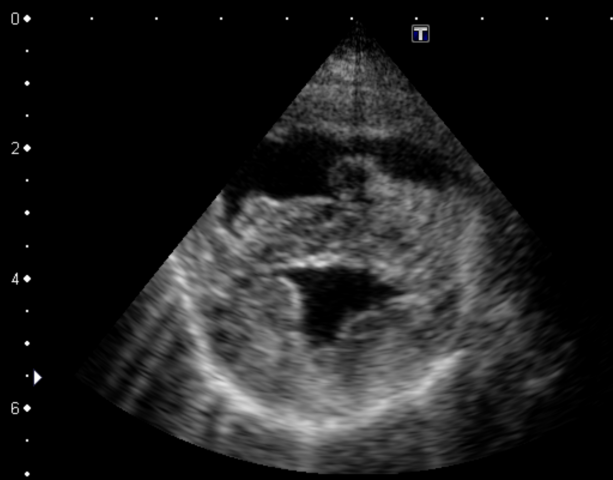

また肺動脈と右心室の拡大、心室中隔の扁平化は、肺高血圧症を診断するための補助的所見として重要です。

(上が右心室の拡大、下が左心室)